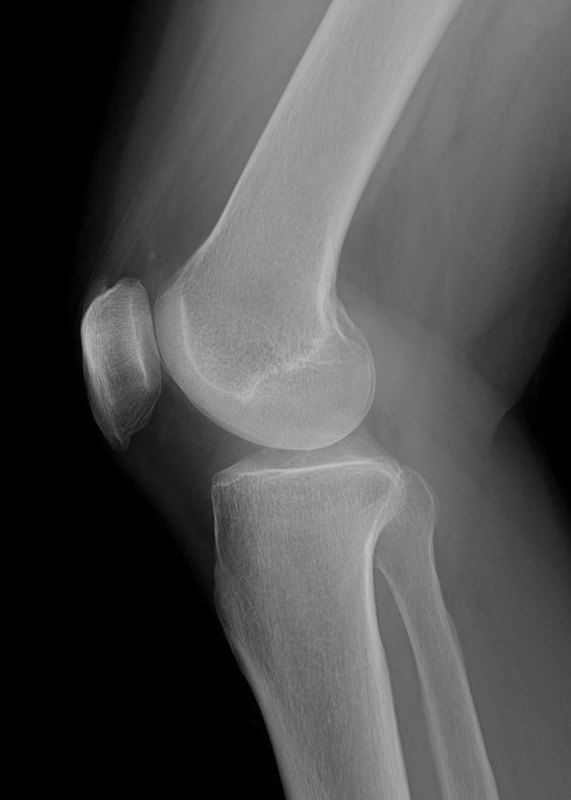

練習を一定期間休むとはれはなくなるが運動量をあげると腫れが出現してしまい試合出場が困難な状態となり治療のため帰国した。XP画像

他院でレントゲンの撮影を行い骨には異常がないと診断され、湿布の処方とヒアルロン酸の治療を5回施行するも効果がなく当院に来院した。XP画像